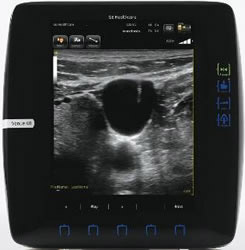

Venue 40 Anesthesiaで撮影した血管穿刺画像